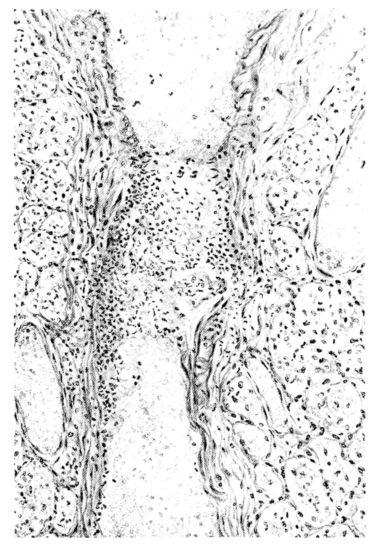

FIG. III. AUTOPSY NO. 90. DRAWING FROM A LESION OF THE TRACHEA (SOMEWHAT OLDER THAN THAT ILLUSTRATED IN FIGURE II). THE MUCOSA IS ENTIRELY LACKING. CONGESTION AND EDEMA ARE THE STRIKING FEATURES IN THE SUBMUCOSA. THE NECROTIZING PROCESS HAS EXTENDED INTO THE MUCUS GLANDS. THIS IS SHOWN IN THE LOWER PICTURE.

The changes are less marked, perhaps, in the trachea than in its finer ramifications. The mucosa is constantly more or less destroyed and large areas, usually focal, are entirely devoid of their epithelial covering. This is replaced by a sparse exudate, composed largely of red blood cells, mucus, a small amount of fibrin, and nuclear fragments (Fig. II). It may dip into the submucosa for a short distance, but usually these indentures are associated with the ducts of the mucous glands into which the inflammatory reaction extends. A more striking feature than the exudate, however, is the edema and the congestion of the submucosa. The loose areolar tissue of the submucosa is spread widely apart, and throughout it distended blood vessels are very conspicuous. Occasionally such a vessel is broken and actual hemorrhage appears in the submucosa. Occasionally, too, the inflammation extends down the duct to the mucous gland itself, and here, also, aplastic inflammatory reaction is evident, inasmuch as the acini now stain intensely red with the cells undifferentiated from each other and specked here and there by broken remains of the dead nuclei (Fig. III). After the disease has continued for a short period, even at the end of five or six days, some regeneration of the epithelial lining may be seen (3) (Fig. IV). But despite this, the acute picture persists, and there goes on, side by side, an attempted repair characterized by epithelial regeneration and the same evidence of acute change. Since the lesion is essentially a superficial one, scars or contractures of any extent are not encountered in the trachea, even in examples of the disease that have ended fatally only after many weeks.[4]